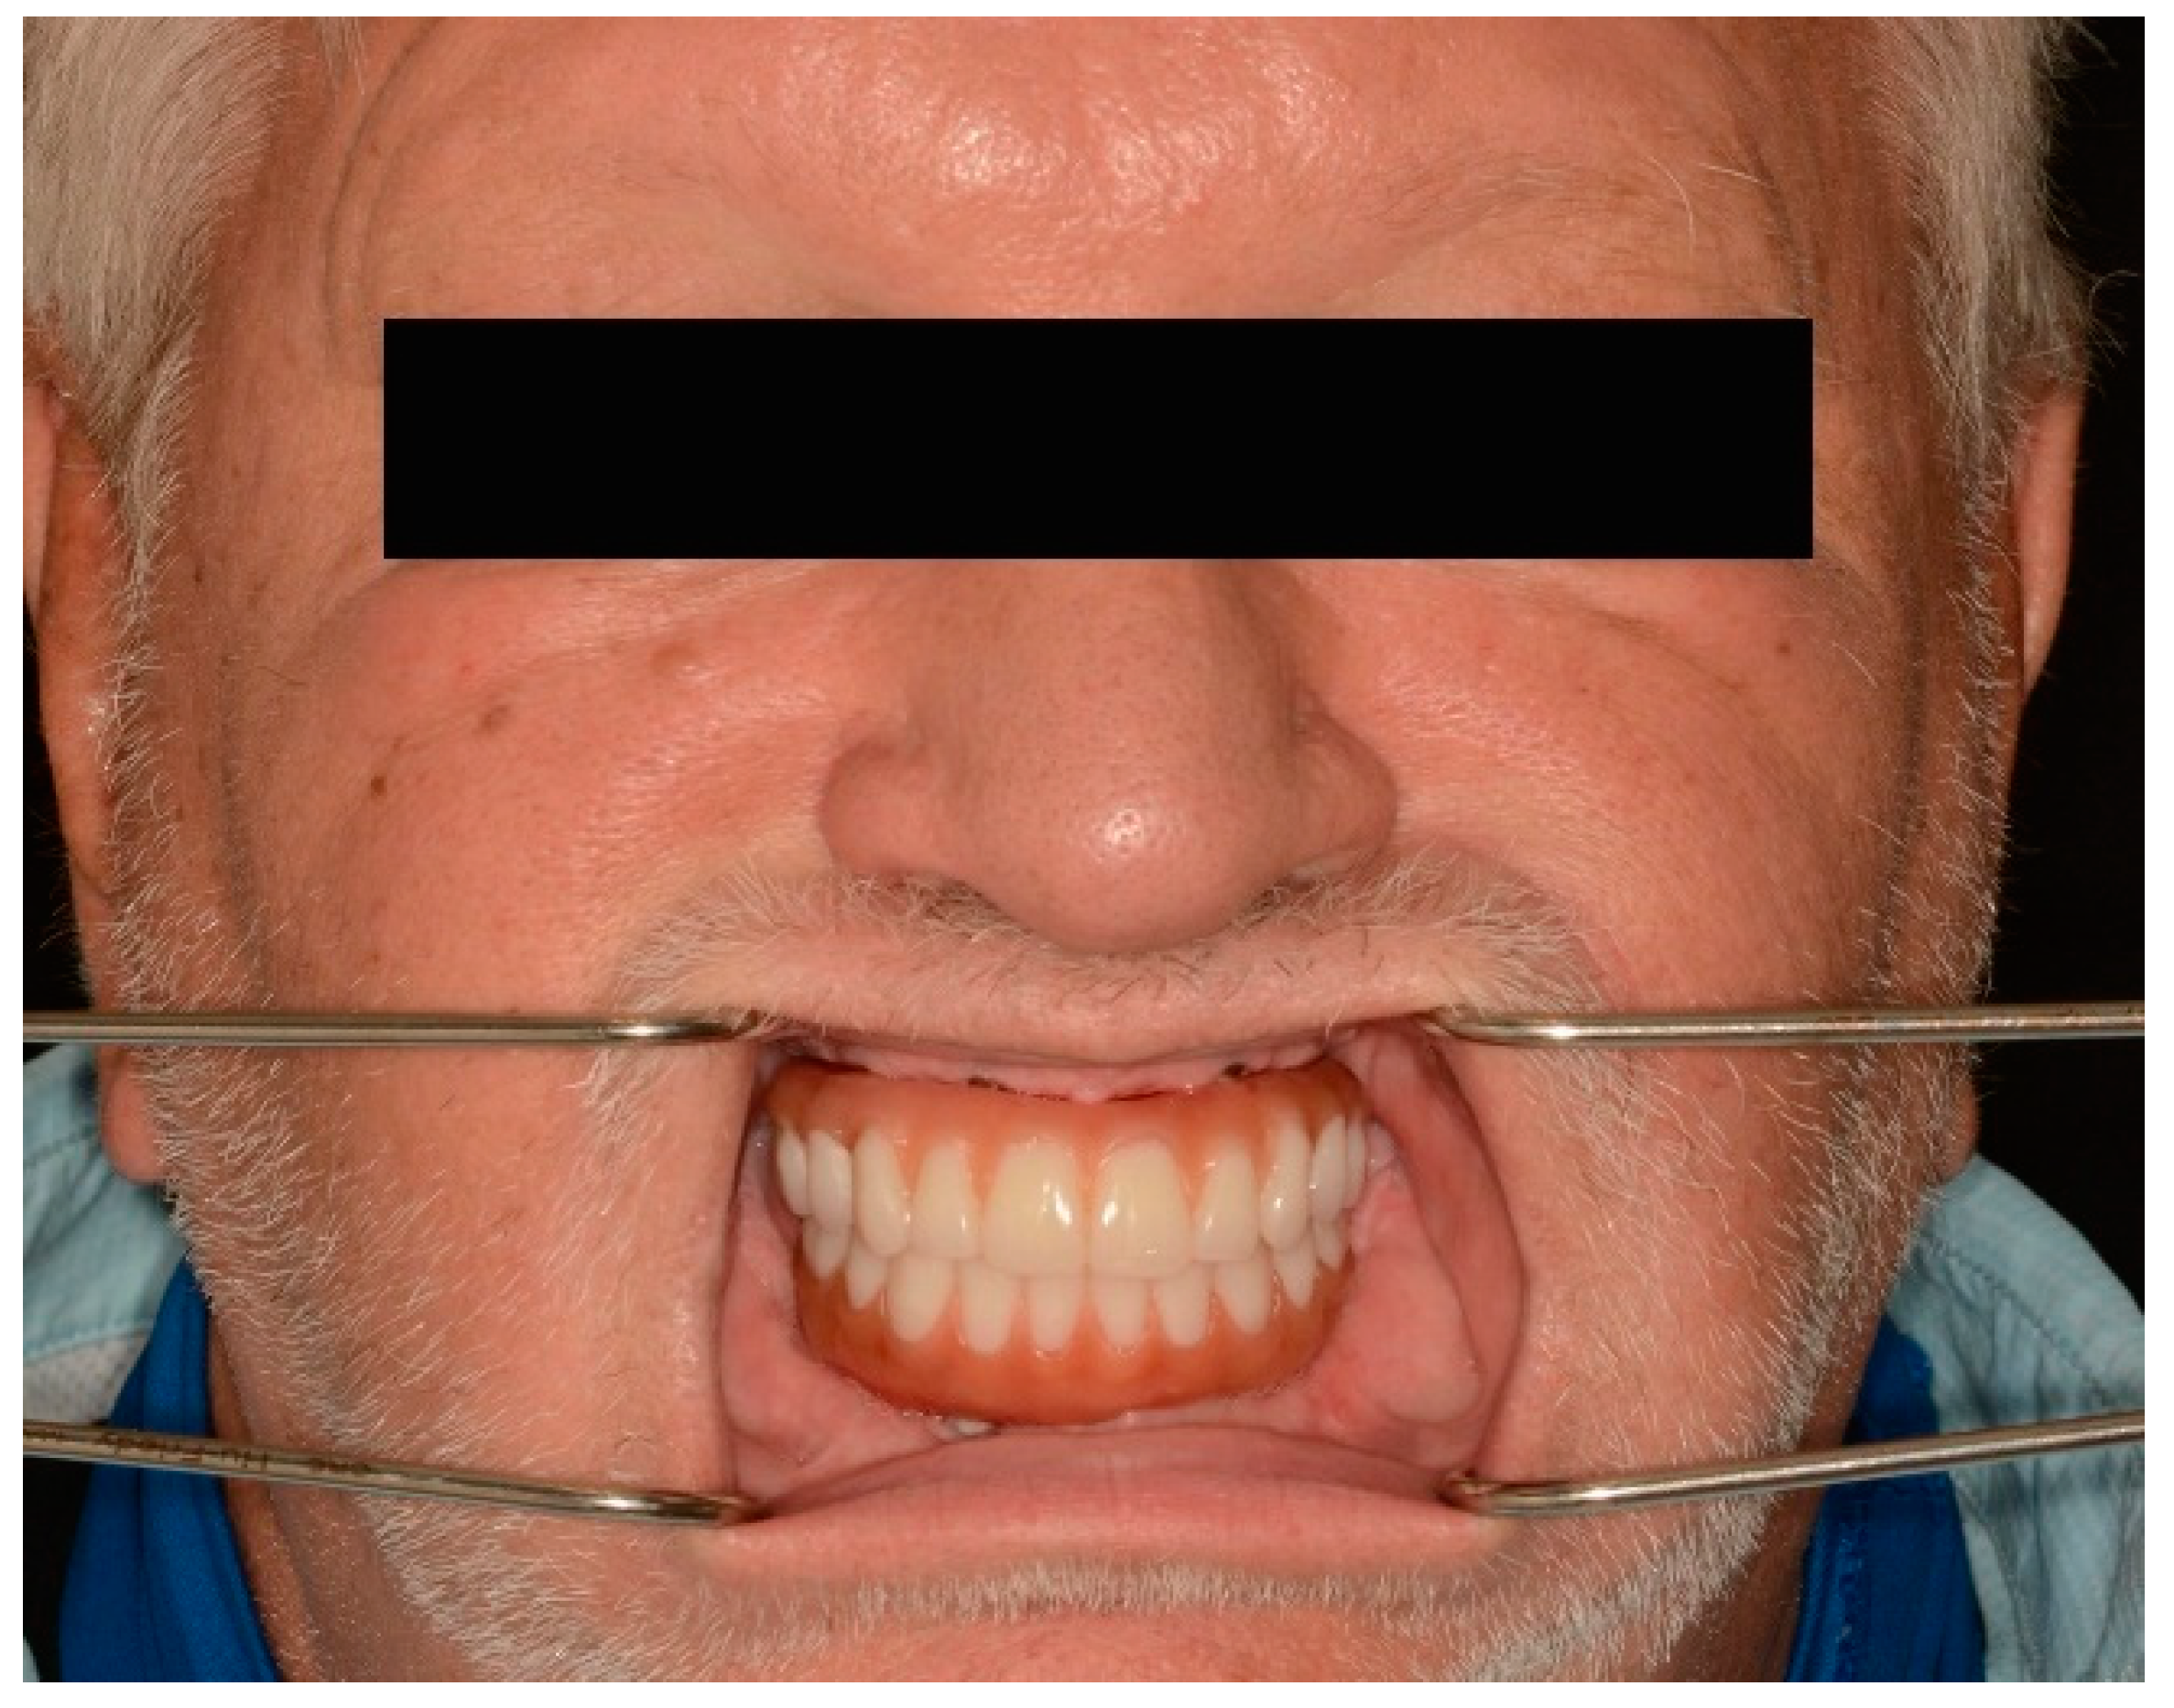

Full-Mouth Rehabilitation of a Patient with Sjogren’s Syndrome with Maxillary Titanium-Zirconia and Mandibular Monolithic Zirconia Implant Prostheses Fabricated with CAD/CAM Technology: A Clinical Report

3. Results